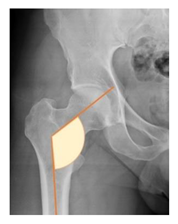

Plain radiographs were evaluated preoperatively and at the most recent follow-up, after appropriate calibration. Positional parameters were assessed according to values guidelines from published literature, as listed in Table 1 [23,24,25,26,27,28,29,30,31]. Femoral stem and acetabular cup osteointegration were quantified according to Engh [32] and Moore scale [33]. Heterotopic ossifications were graded according to the Brooker system [34].

3.4. Radiographic Evaluation

Preoperative and postoperative radiographic data are reported in Table 4. Preoperatively, 18 THR (24.3%) were implanted in skeletally immature children with closed triradiate cartilage (1 ≤ Risser ≤ 3). Radiographic acetabular insufficiency (LCEA < 25° and AI > 13°) was detected in 14 hips (18.9%), while protrusion was present in 3 hips (4.1%) An excessive valgus of the femoral neck was observed in 19 hips (25.7%), while an important varus deformity was present in 7 hips (9.5%).

Preoperative and postoperative radiographic parameters. All results are expressed as crude numbers for dichotomous variables and as mean ± Standard Deviation for continue variables. LCEA: Lateral center-edge angle. * Varus inclination is expressed as negative value, positive value for valgus.

Postoperative radiographs showed a significant vertical malposition of the cup in 1 case (1.4%), a significant varus stem in 8 cases (10.8%) and a significant valgus stem in 1 case (1.4%). Two patients (2.7%) showed moderate heterotopic bone formation (Brooker ≥ 2), that did not significantly affect the hip motion and symptoms. All those THR that did not undergo revision showed good radiographic osteointegration, with no evidence of implant breakage, radiographic lucencies, bone defects, cup migration, or stem subsidence at the most recent radiographs.

In our experience, implant malposition was the only reason for implant revision. In one case, progressive subsidence was observed in a varus undersized stem, implanted in a boy with Albers–Schömberg disease; in another case, an excessively vertical cup with a 28 mm femoral head caused hip instability and required cup revision.

THR can be a challenging procedure in very young people. The combination of distorted anatomy, small physique, and poor bone stock can impede proper implant placement. Implant sizing may be an issue in these patients. The combination of young age and peculiar conditions such as skeletal dysplasia may require particular attention in preoperative planning and implant selection. Noticeably, we used the smallest size of the cup in 11 hips (15%) and the smallest size of the stem in 14 hips (19%). A meticulous preoperative planning, even using simulation software, [40,41,42] and careful implant selection, sometimes requiring even customized implants [37], is crucial in such conditions, to prevent unpleasant pitfalls during the operation.